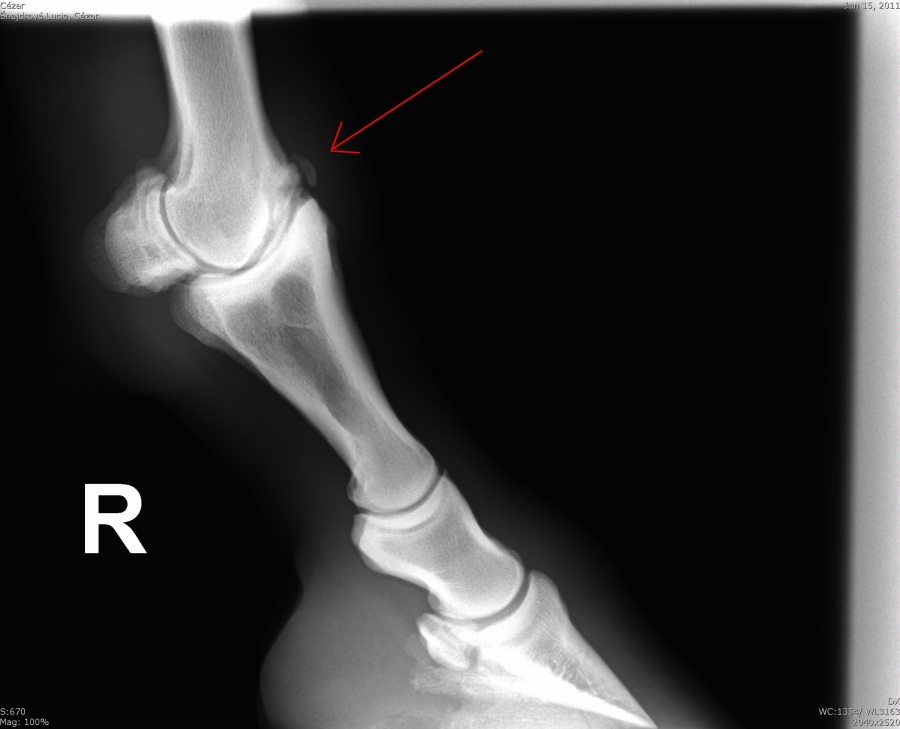

Fragment na spěnkové kosti